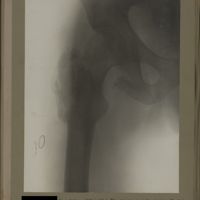

0151 - Page 39 - [Radiographie de la hanche]0151 - Page 39 - [Radiographie de la hanche]